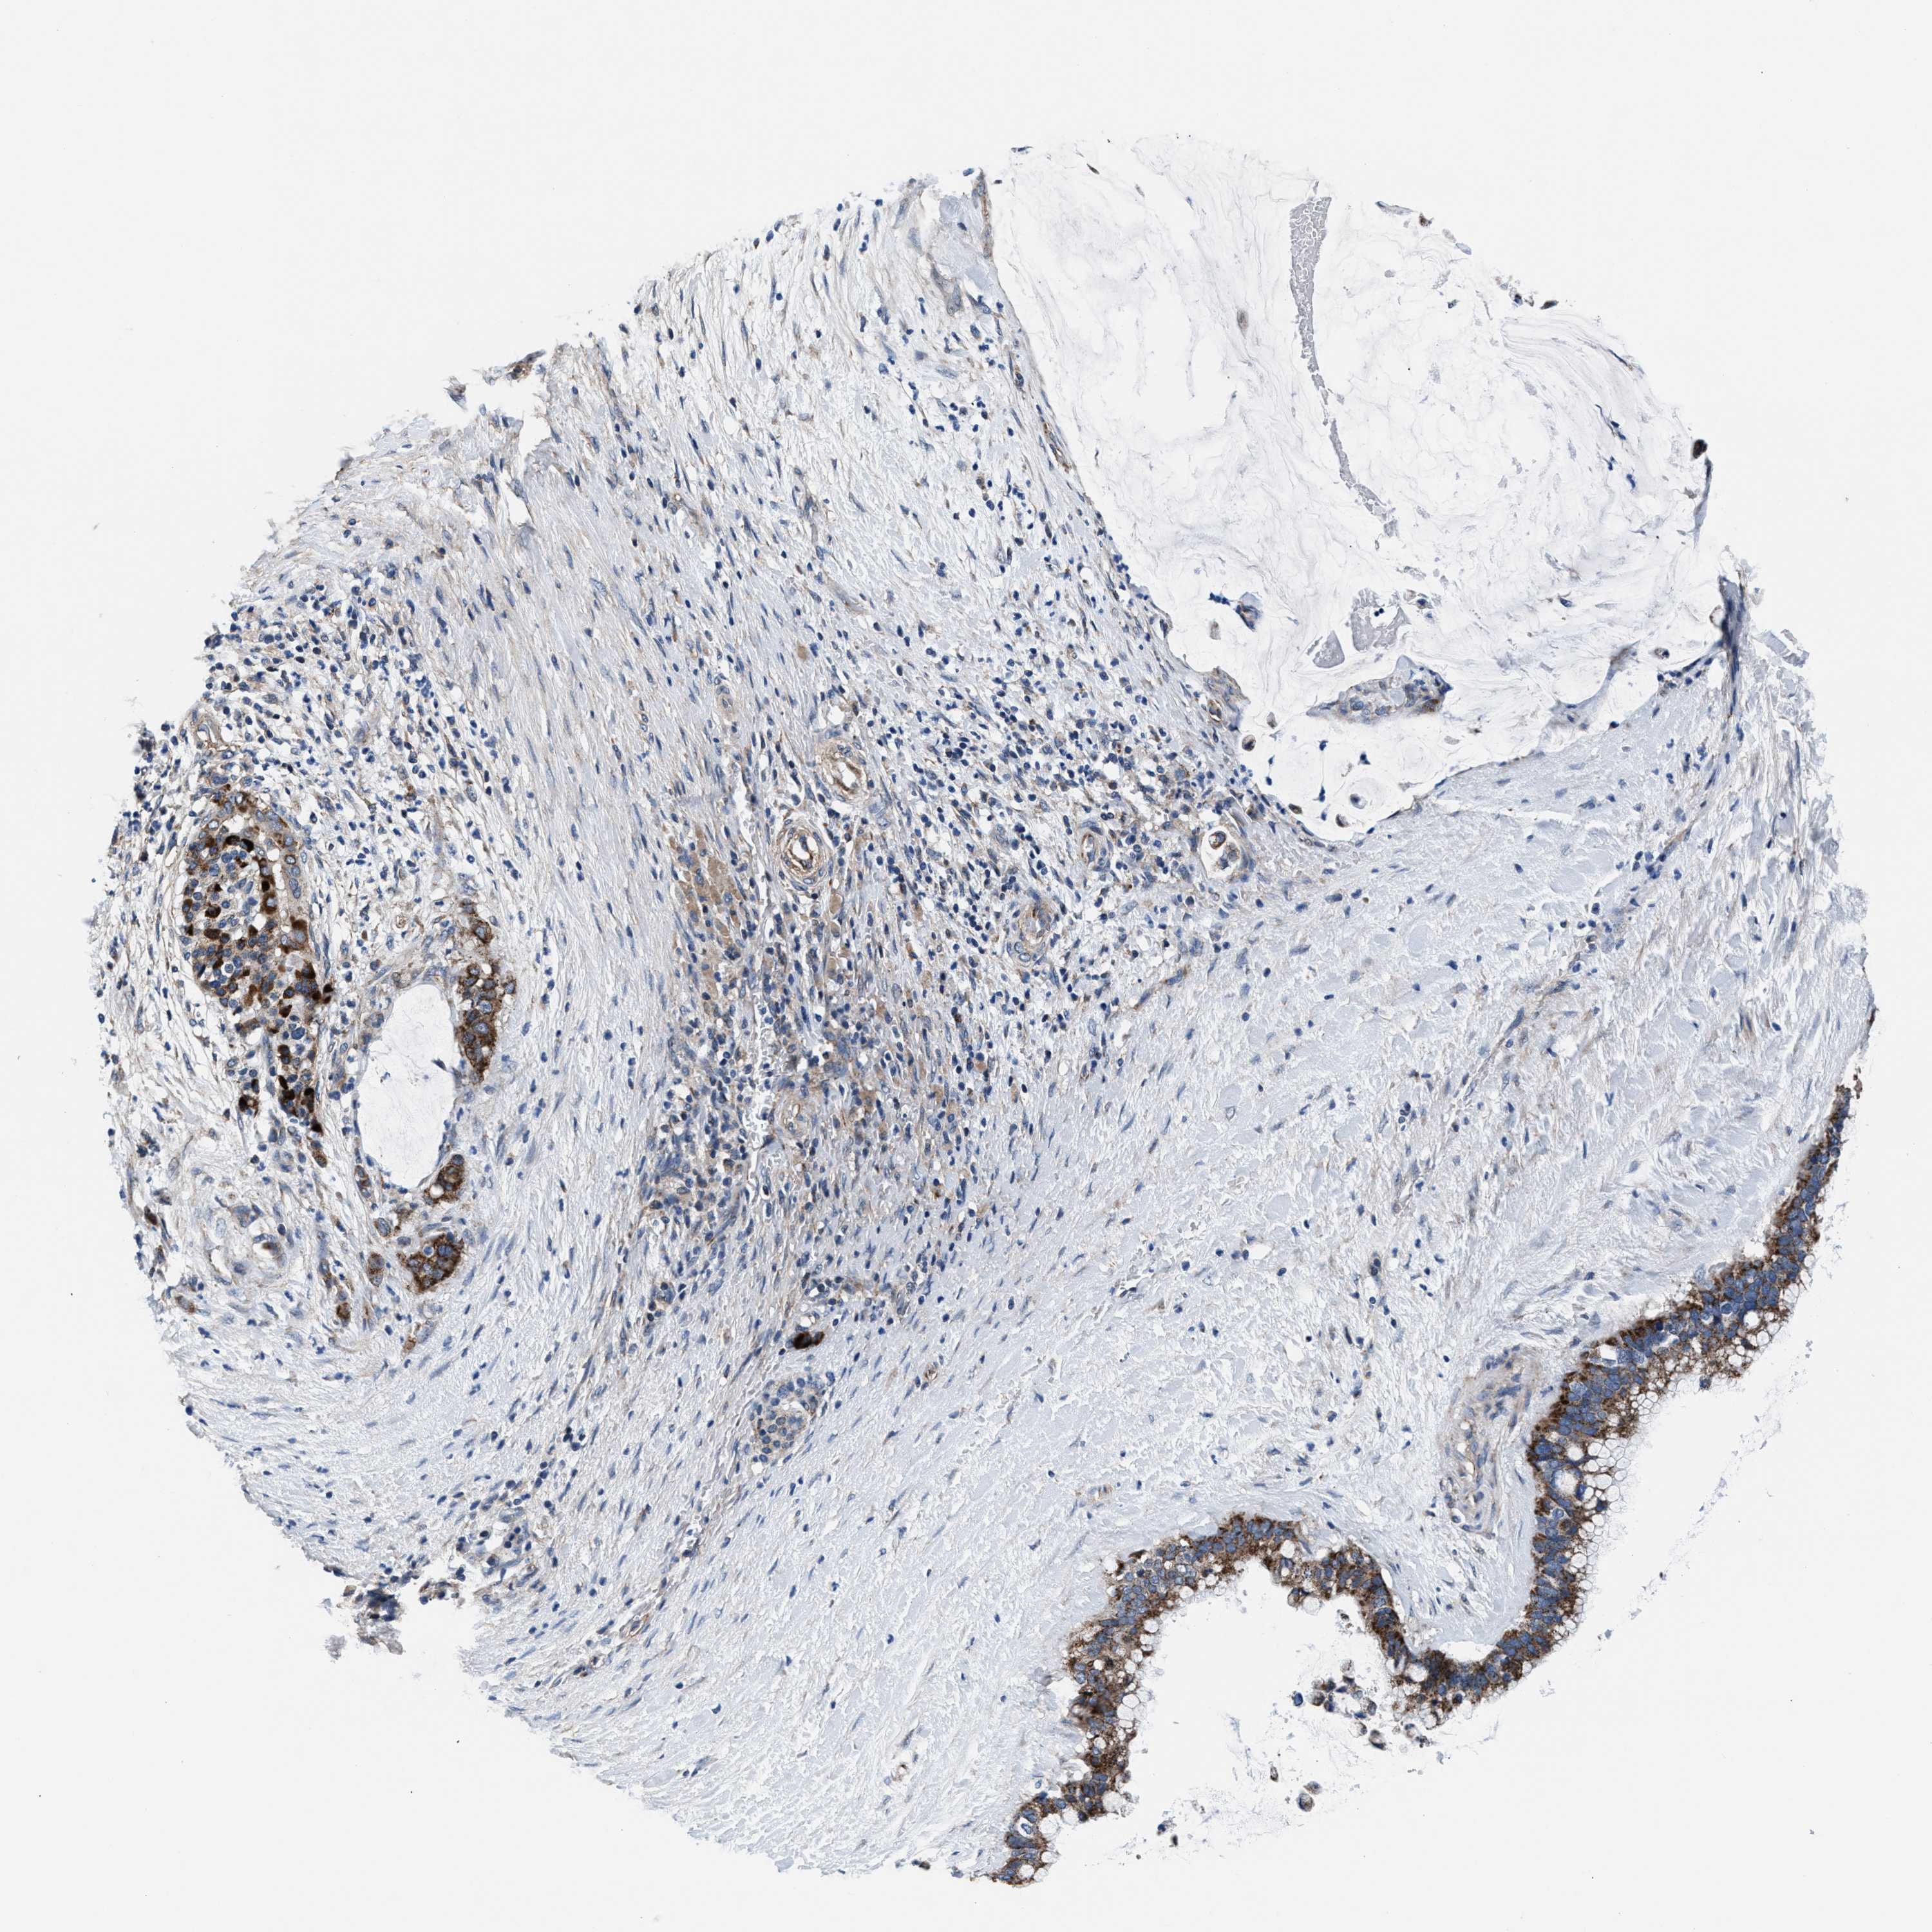

PANCREATIC CANCER - Protein expressioni

A mouse-over function shows sample information and annotation data. Click on an image to view it in a full screen mode. Samples can be filtered based on level of antibody staining by selecting one or several of the following categories: high, medium, low and not detected. The assay and annotation is described here.

Note that samples used for immunohistochemistry by the Human Protein Atlas do not correspond to samples in the TCGA dataset.

Antibody stainingi

Antibody staining in the annotated cell types in the current human tissue is reported as not detected, low, medium, or high, based on conventional immunohistochemistry profiling in selected tissues. This score is based on the combination of the staining intensity and fraction of stained cells.

Each image is clickable and will lead to virtual microscopy that enables deeper exploration of all samples and also displays staining intensity scores, fraction scores and subcellular localization as well as patient and tissue information for each sample.

Antibody HPA022120

Staining

High

Medium

Low

Not detected

Intensity

Strong

Moderate

Weak

Negative

Quantity

>75%

75%-25%

<25%

None

Location

Nuclear

Cytoplasmic/membranous

Cytoplasmic/membranous,nuclear

Adenocarcinoma, NOS